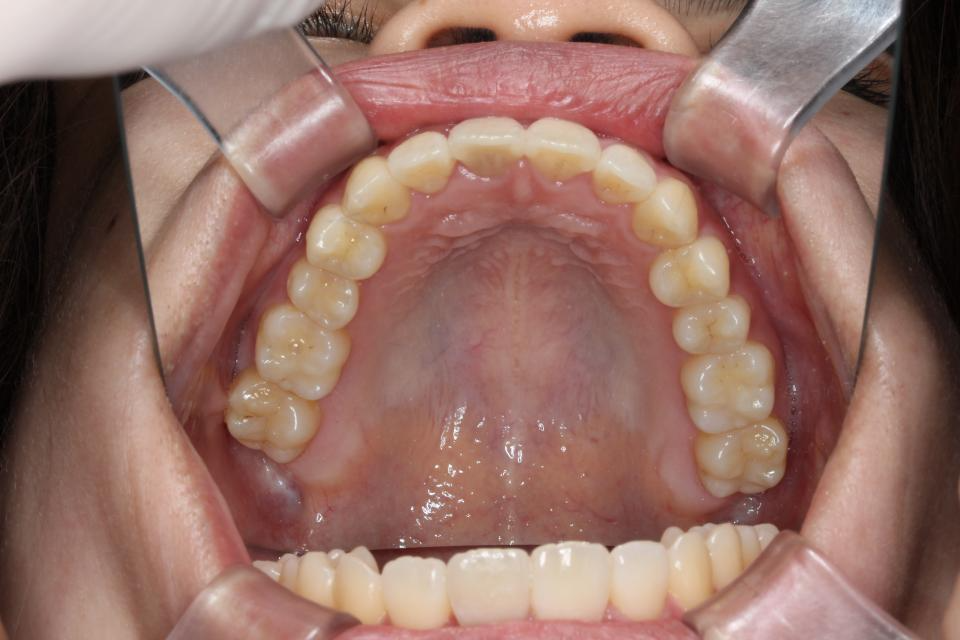

矯正治療前

前歯が出ているのと隙間が気になる、と当院に来院されました。

目立たない装置・取り外し可能なマウスピースタイプでの矯正治療を

希望されてましたので親知らずを4本抜歯して、歯のやすりがけ(IPR)をし、マウスピース型矯正装置(インビザライン)で矯正治療を行いました。

| 年齢・性別 | 20代女性 |

|---|---|

| 矯正治療期間 | 2年3か月 |

| 抜歯の有無 | 上下左右親知らず抜歯 |

| 治療費 | 1005000円 |

| リスク・注意点 |

歯の移動に伴い痛みを感じる場合がある 治療後保定装置を使わないと後戻りを生じる

|